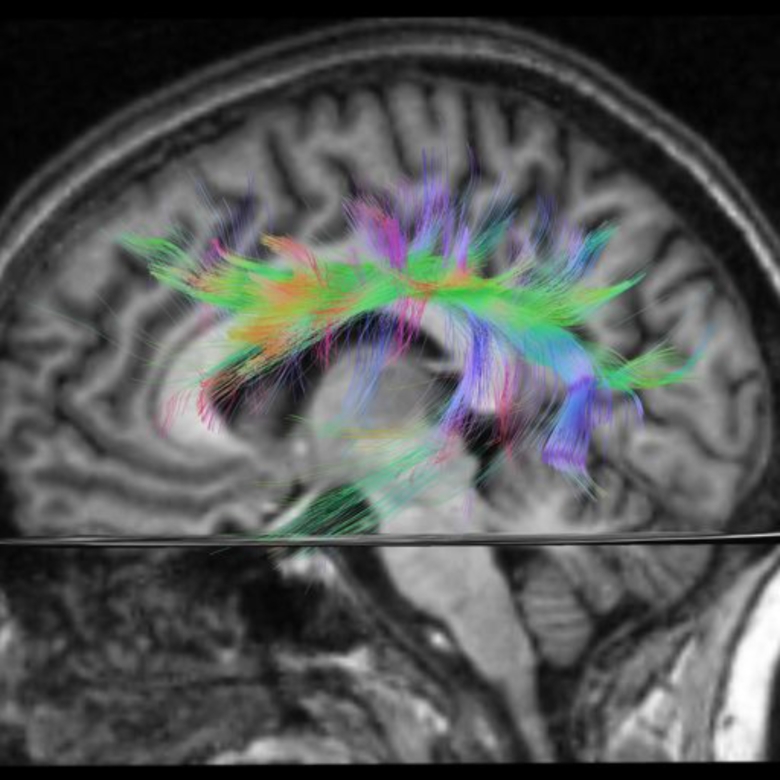

Тем не менее билингвизм действительно меняет наш мозг. Еще в 2004 году группа ученых из нескольких британских университетов в своей работе показала, что владение несколькими языками вызывает «скорее функциональные, чем структурные» изменения мозга. Они установили, что изучение второго языка увеличивает плотность серого вещества (состоящего из нейронов, обрабатывающих информацию) в нижней части теменной доли левого полушария, которое отвечает за языковые и коммуникативные навыки. Более того, эффект зависит от уровня владения языками и возраста, в котором человек начал их изучать, – эти изменения были максимально выражены у людей, начавших изучать второй язык до пятилетнего возраста, и тех, кто владел вторым языком наиболее свободно. Более поздние исследования подтвердили эти выводы.